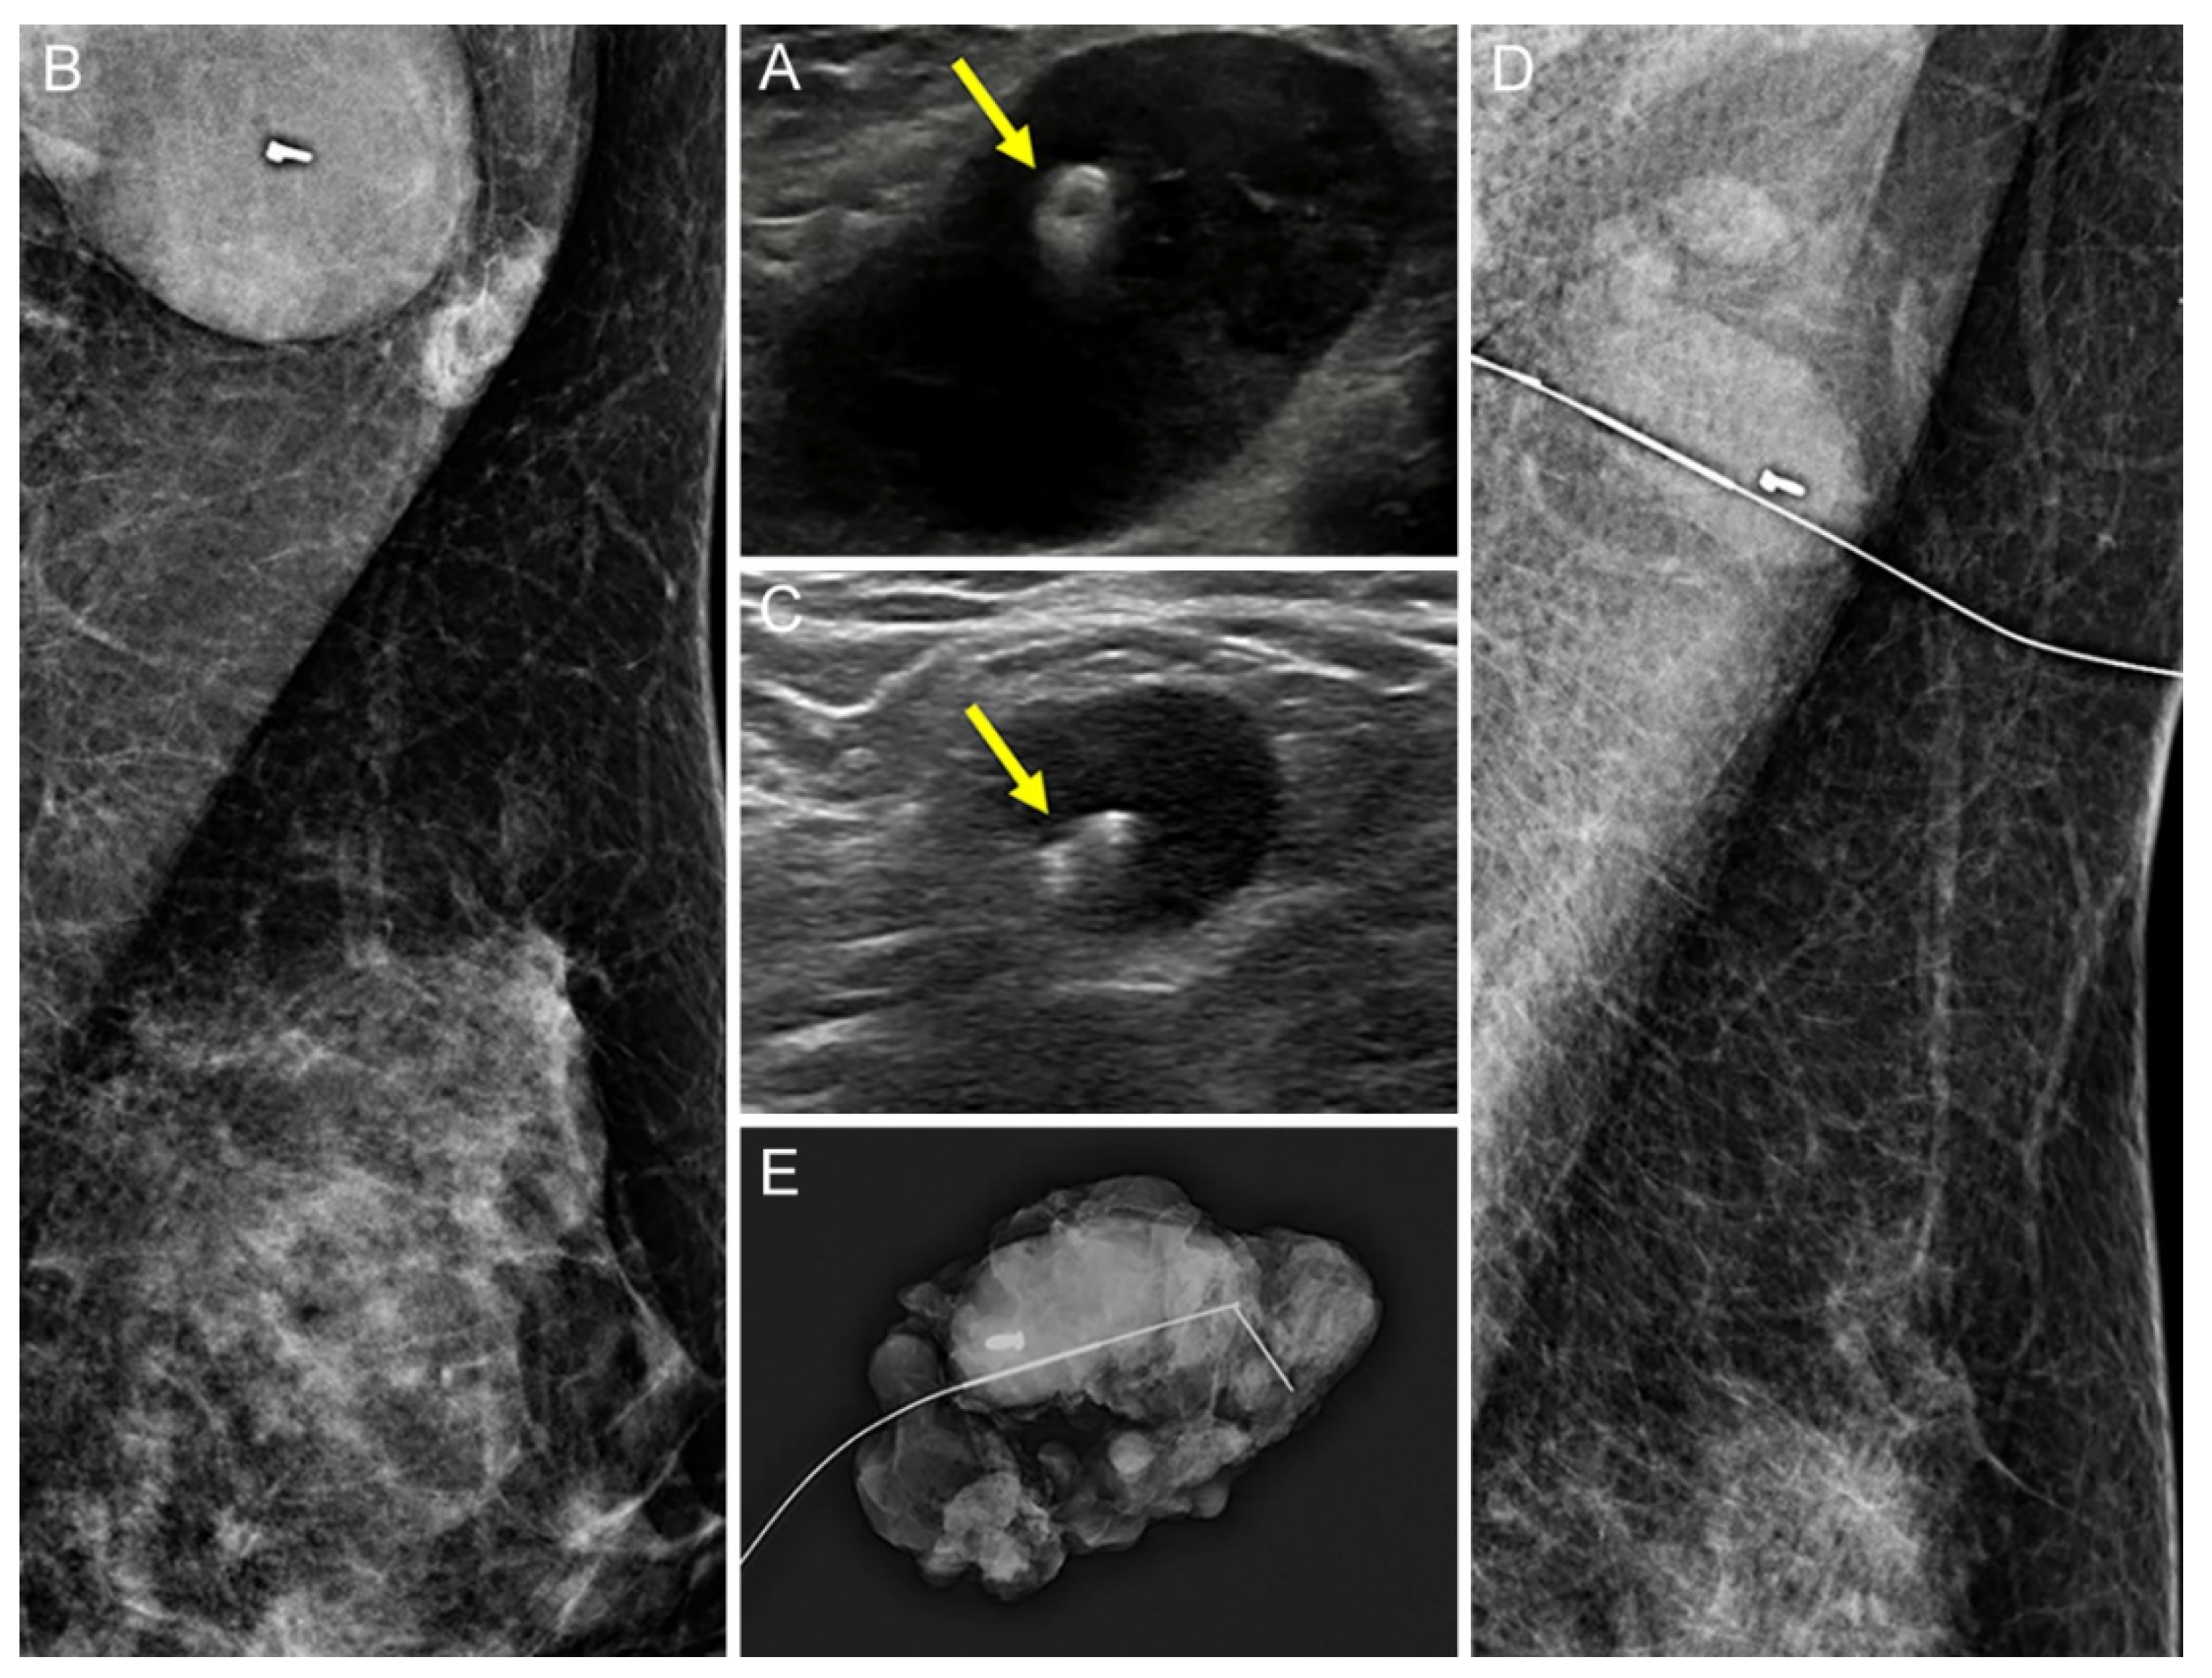

2.2. Tissue Marker Insertion for Axillary Lymph Nodes before NAC

2.3. Localization of Tissue Marker-Inserted Axillary Lymph Nodes after NAC